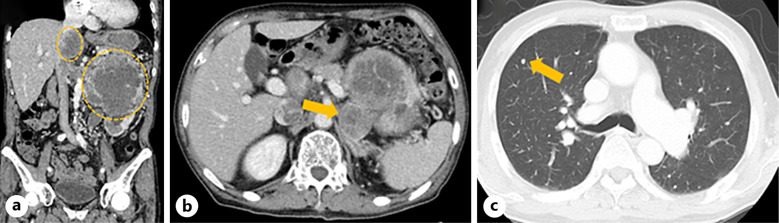

Case presentation: We encountered a case of advanced renal cancer in which immune checkpoint inhibitor-associated myocarditis was confirmed on autopsy. A 78-year-old man was diagnosed with a left renal tumor secondary to hematuria. A tumor biopsy was performed, and the tumor was diagnosed as cT4N0M1 clear cell renal carcinoma, which was classified as poor risk by the International mRCC Database Consortium. Combination therapy with pembrolizumab and axitinib was initiated. One month later, the patient developed anorexia, dizziness, and fatigue, which were judged to be adverse events due to systemic therapy, and the patient was admitted to the hospital urgently. After admission, the patient experienced a sudden drop in blood pressure and loss of consciousness and was referred to a cardiologist for treatment. Blood tests showed elevated brain-type natriuretic peptide levels, but echocardiography showed good cardiac function. However, soon thereafter, the patient developed tachycardia, and echocardiography revealed a significant decline in systolic function, leading to the diagnosis of immune checkpoint inhibitor-associated myocarditis. Despite intensive care in the cardiac high-care unit and steroid administration, the patient died. An autopsy revealed necrotic changes in the myocardium, loss of myocardial cells, and severe lymphocyte infiltration, leading to a diagnosis of inhibitor-associated myocarditis.